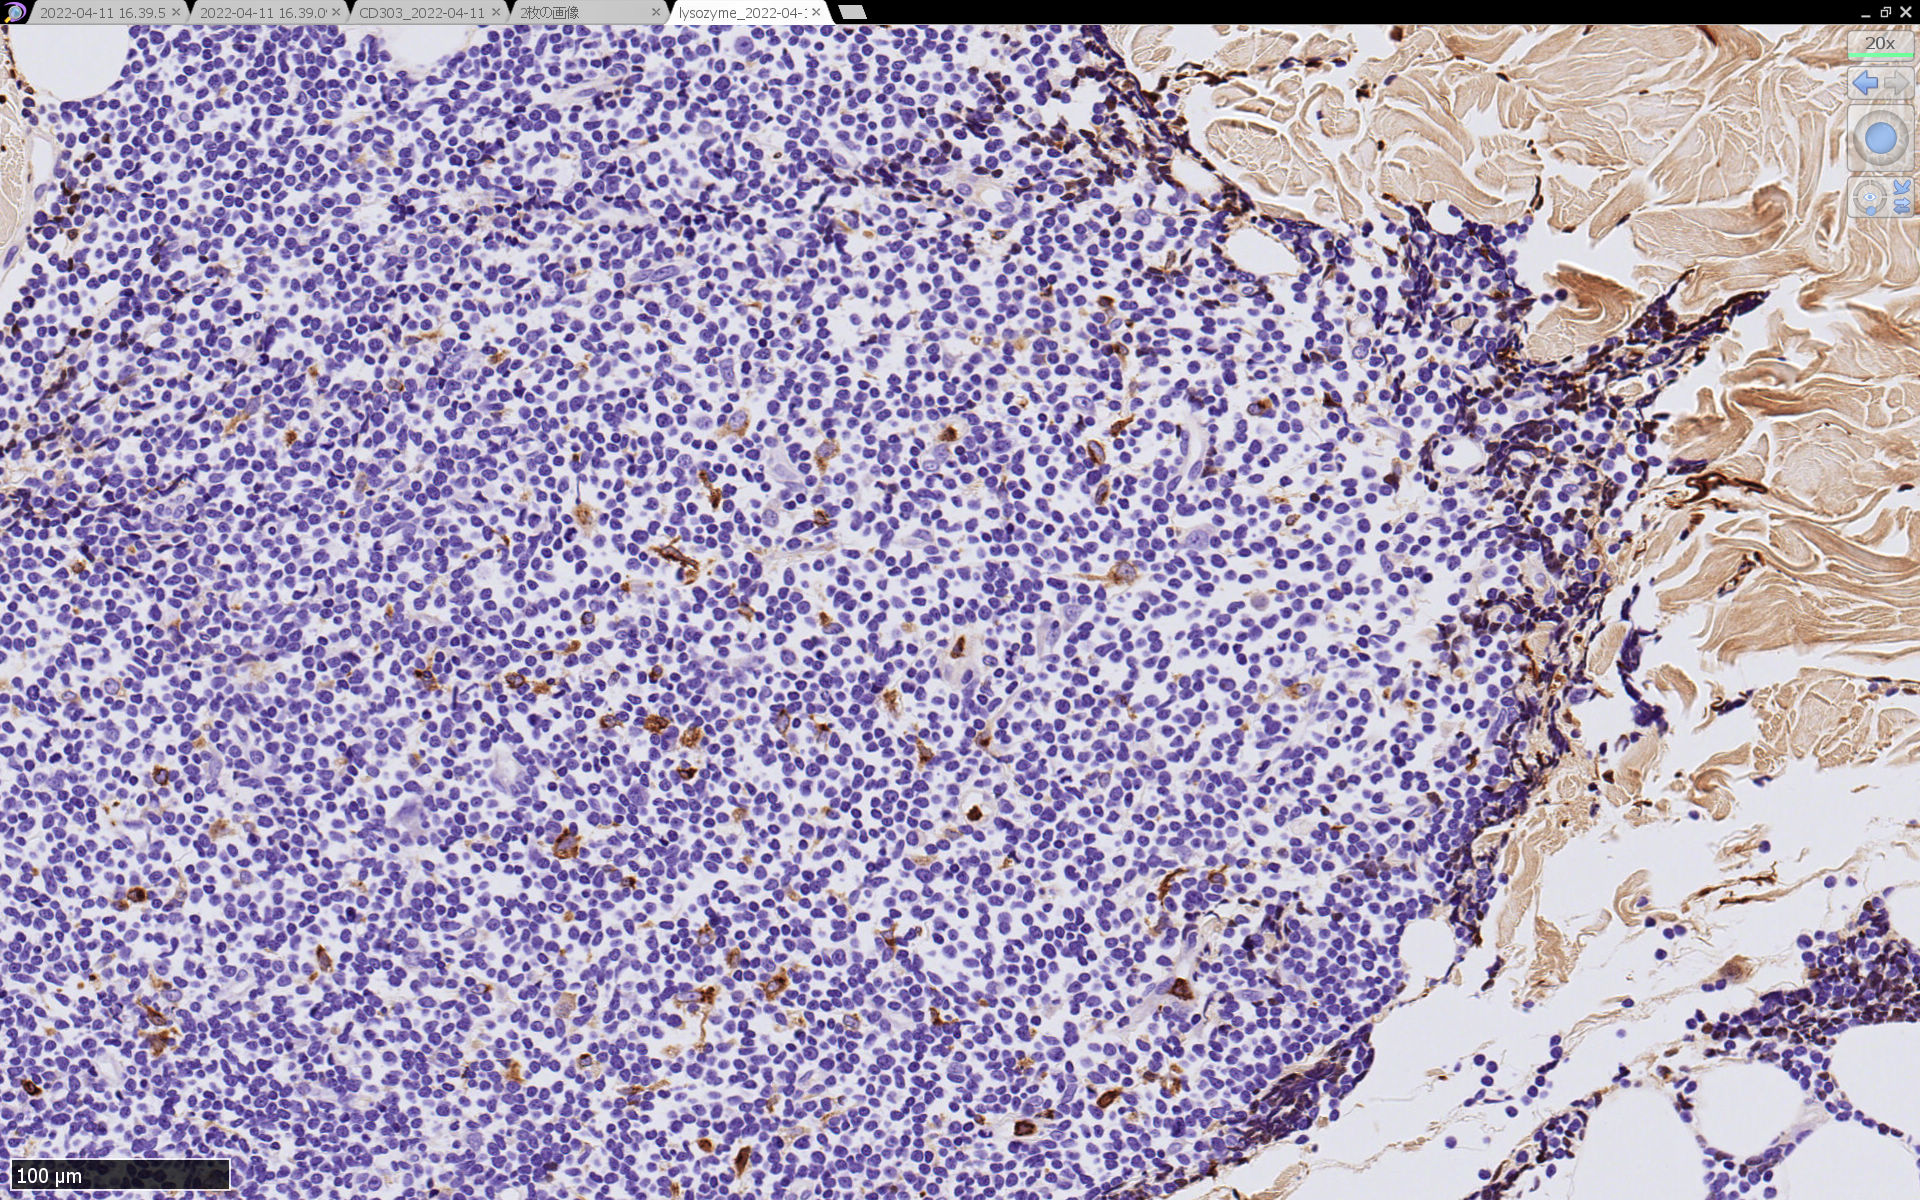

皮膚病変

blasticという名前から「大型細胞」を想起するが, この症例のようなclassical typeの細胞は思ったほど大きくはない. CD123陰性リンパ球とくらべてもあまり大きくないことがわかる.(散在する大型細胞はlysozyme+)

形態は均一で多型はめだたない.

免疫染色

腫瘍細胞は真皮を主座として, 皮下脂肪織まで, びまん性かつ単調monotonousに増殖することが多く, 表皮向性はみられない. 本例では血管や付属器中心あるいは脂肪織内に結節状の浸潤増殖を示した.

本例皮膚真皮増殖細胞はCD4+, CD56+, CD123+, CD303+, lysozyme(-). がん研有明病院, Sakamoto K, Takeuchi K先生にconsultationを行い, TCF4, TCL1の陽性が確認された.(consultationを受けていただいた両先生に深謝いたします.)

BDCA-2(CD303)